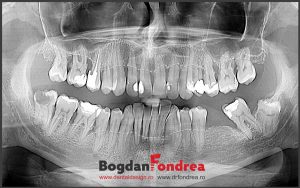

Planificarea implanturilor dentare

Nu e deloc complicat sa faci o gaura in perete si sa introduci un surub in...